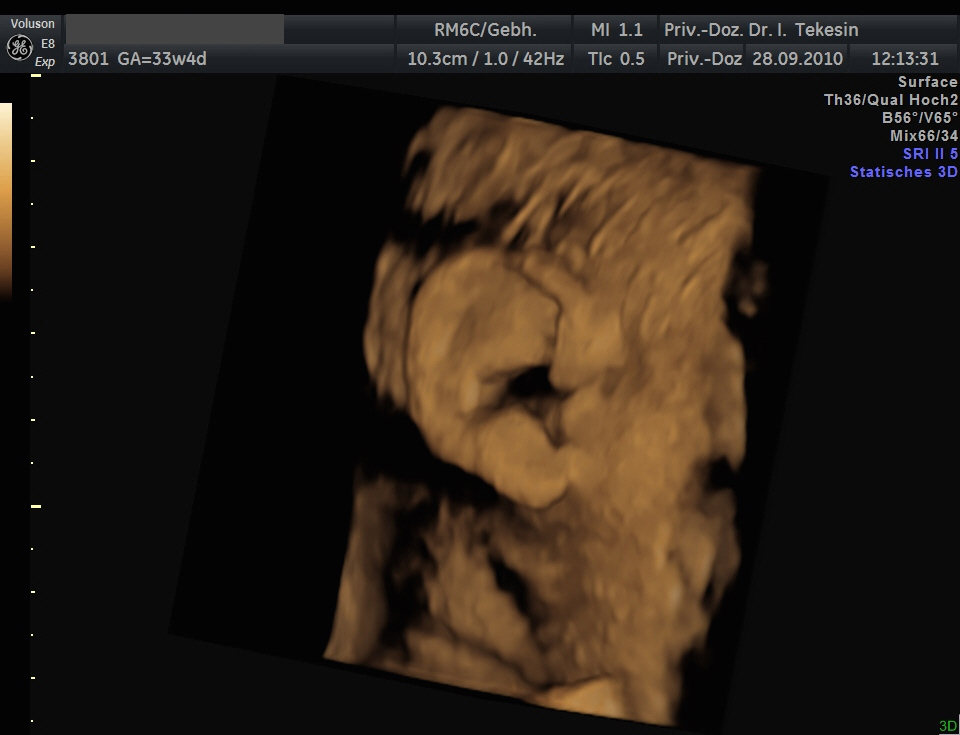

3D-/4D-Ultraschall (optional)

Immer mehr werdende Eltern interessieren sich für die faszinierenden Bilder, die dieses Verfahren liefert. Die plastische, dreidimensionale Darstellung der Oberfläche des Gesichts und anderer Körperregionen wird durch spezielle Bildrekonstruktion in schnellen Rechnern erreicht. Auch einzelne innere Organe oder „Gefäßbäume“ können von allen Seiten betrachtet werden. Viele dünne Schnittebenen (2D) werden zu einer gemeinsamen 3D-Sichtweise im Computer des Ultraschallgerätes zusammengeführt. Unter einem 4D-Ultraschall versteht man darüber hinaus eine 3D-Ultraschalluntersuchung unter Echtzeitbedingungen. Anstatt nur statische Bilder anzuzeigen, erfasst ein 4D-Ultraschall die Bewegungen des Kindes, weshalb er auch als „Live-3D-Ultraschall“ bezeichnet wird.

Diese Vorgehensweise ermöglicht äußerst realistische Bilder, bei denen sogar Gestik und Mimik des Kindes in bewegten Sequenzen festgehalten werden können. Die Untersuchung kann wie auch der normale Ultraschall während des gesamten Schwangerschaftszeitraums durchgeführt werden. Möchte man das Ungeborene komplett sehen, wird die 12. bis 16. Schwangerschaftswoche empfohlen, die Zeit zwischen der 28. und 33. Schwangerschaftswoche eignet sich besonders zur präzisen Darstellung einzelner Körperteile

Ohr und Haare in der 34. Woche

Ohr und Haare in der 34. Woche (3D-Darstellung)